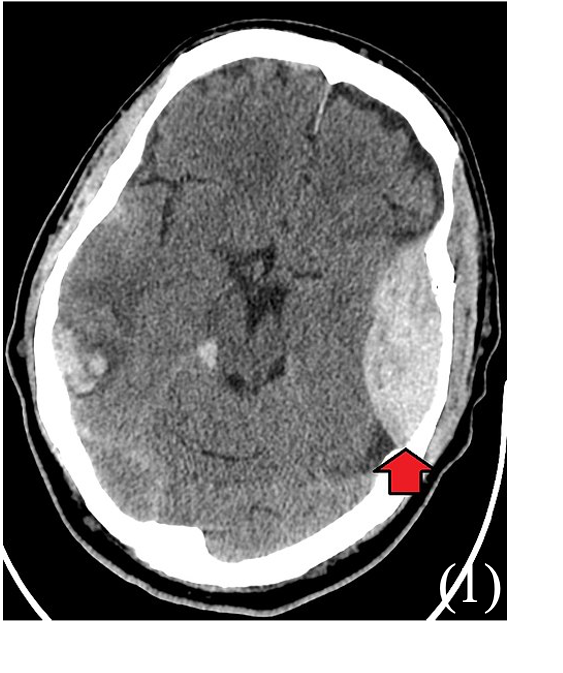

Extradural Haematoma

An extradural haematoma is a bleed into the “potential” space between the dura mater meningeal layer and the inner surface of the skull.

It usually occurs due to low impact trauma to the side of the head, resulting in laceration of the middle meningeal artery running deep to the pterion.

This causes the dura to peel away from the inner layer of the skull. As the bleed enlarges it compresses the brain and raises intracranial pressure causing symptoms.

Non-contrast CT is first-line – shows biconvex, high-density area or “lemon” sign which does not cross suture lines